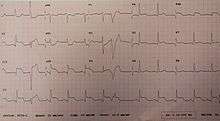

Electrocardiogram

For a person to qualify as having a STEMI, in addition to reported angina, the ECG must show new ST elevation in two or more adjacent ECG leads.[16] This must be greater than 2 mm (0.2 mV) for males and greater than 1.5 mm (0.15 mV) in females if in leads V2 and V3 or greater than 1 mm (0.1 mV) if it is in other ECG leads.[16] Previously, a recent left bundle branch block was considered the same as ST elevation, however, this is no longer the case.[16] In early STEMIs there may just be peaked T waves with ST elevation developing later.[16]